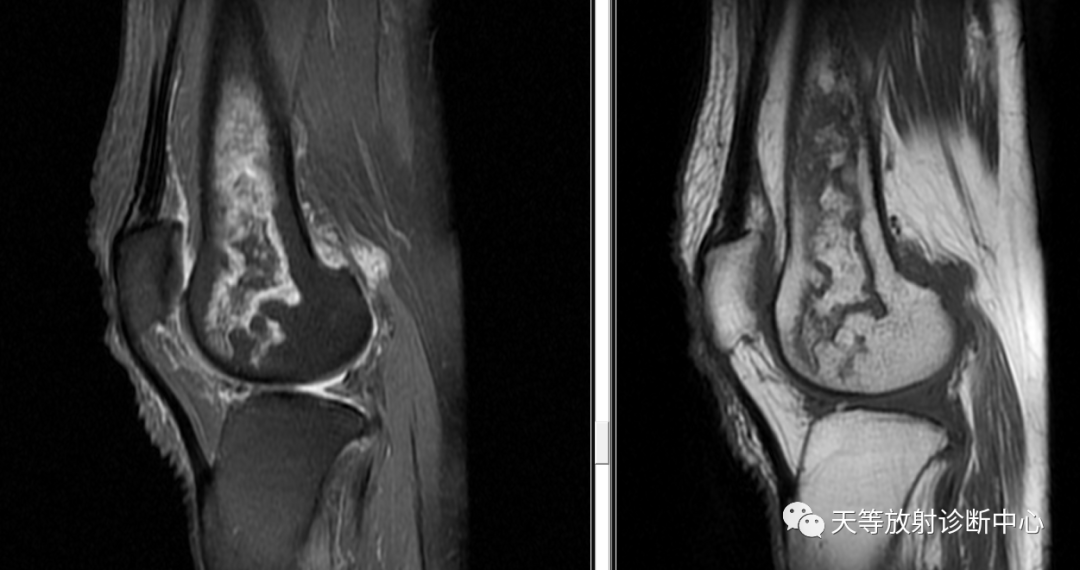

典型征象是病灶边缘呈“三环征”,由外向内,T1WI呈低-高-低,压脂T2WI 高-低-高。

梗死MRI具有特征性表现

如其松质骨内的类圆形或不规则“地图征”、“双线征”或“三线征”表现,MRI是诊断早期骨梗死的金标准,是早期发现、早期诊断骨梗死较准确有效方法。表现不典型者需与急慢性骨髓炎、骨挫伤、恶性骨肿瘤及骨纤维结构不良等鉴别。急性骨髓炎在临床主要表现临床有红肿、热、痛等症状,急性期骨髓腔内见局限性的长TI、长T2 信号,以及明显骨膜反应和骨质破坏,周围软组织肿胀,慢性期可出现骨质增生、窦道、死骨和包壳形成,而骨梗死不累及骨皮质,无明显骨膜反应,周围软组织肿胀较轻。